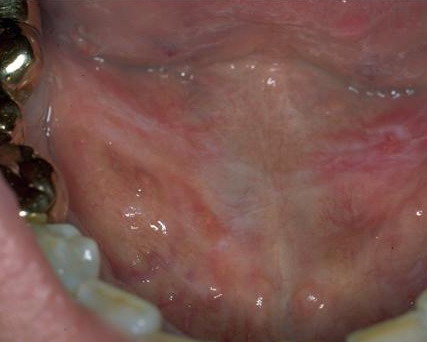

Leucoplakia Praecancerosa = الطلاوة ماقبل السرطانية